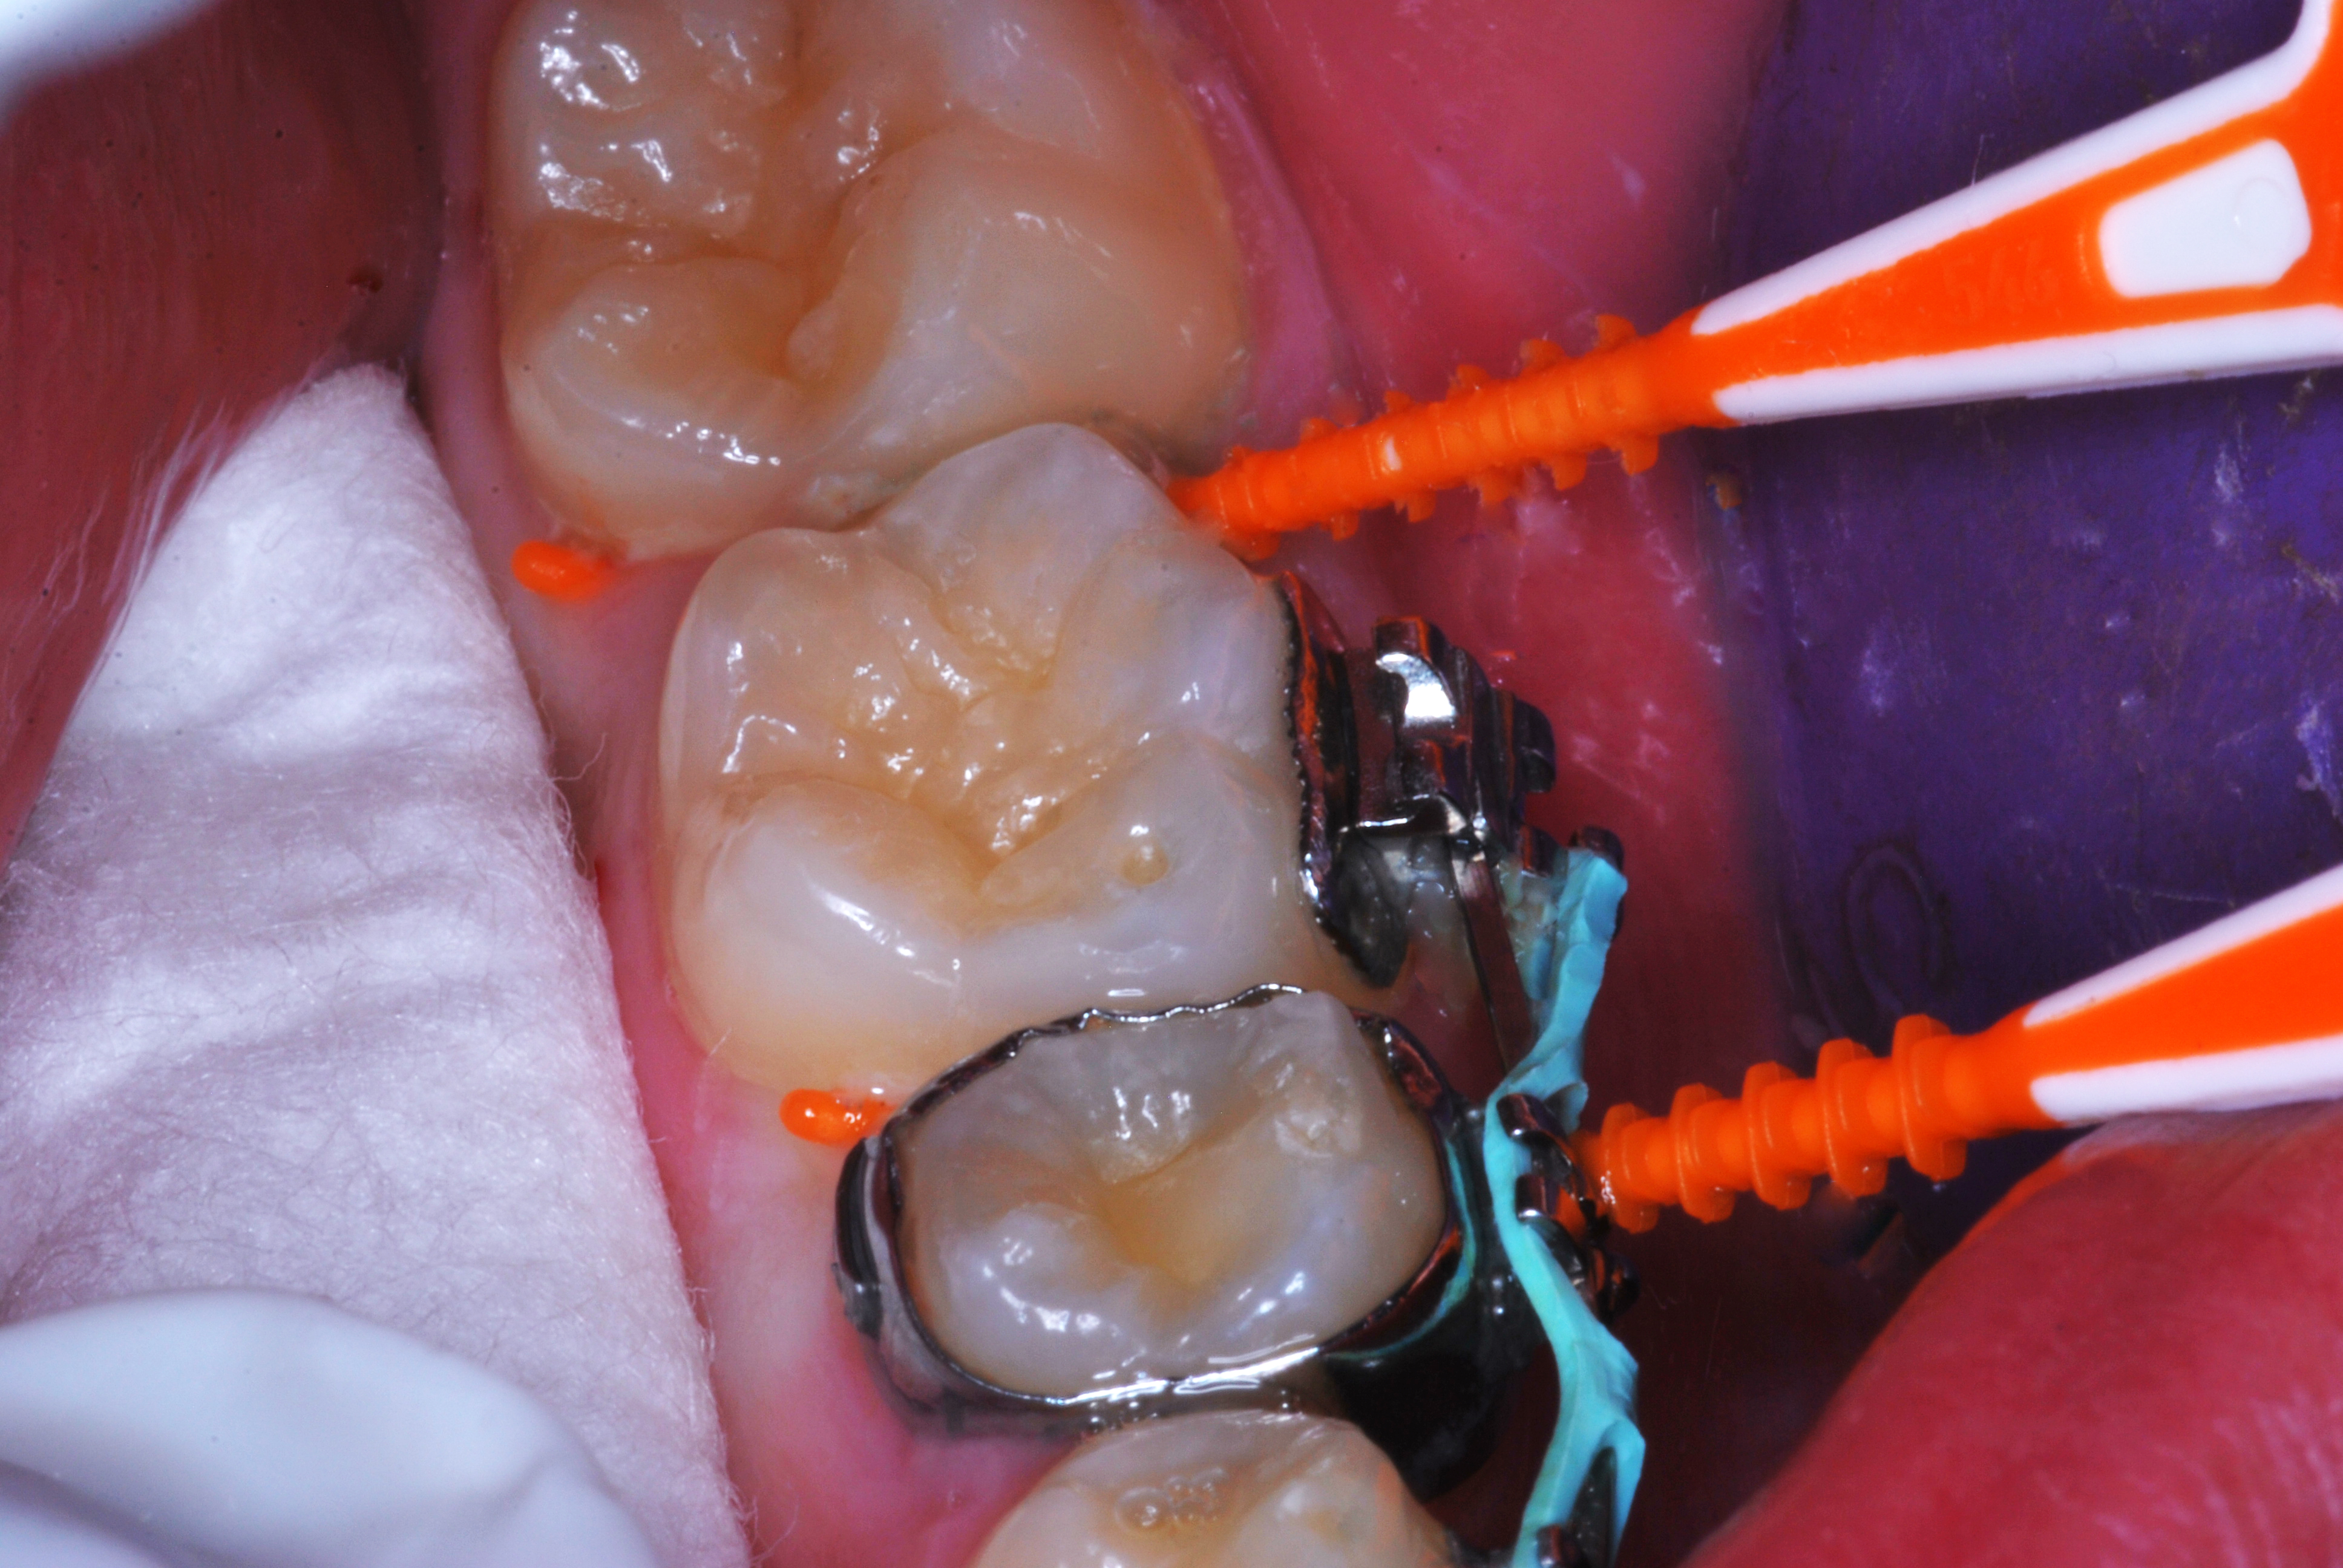

(20.) SDF proximal applications for small first and second molar caries lesions in teenage orthodontic patient, followed by preventive fluoride varnish cover of the area.

Figure 20

(21.) SDF proximal applications for small first and second molar caries lesions in teenage orthodontic patient, followed by preventive fluoride varnish cover of the area.

Figure 21